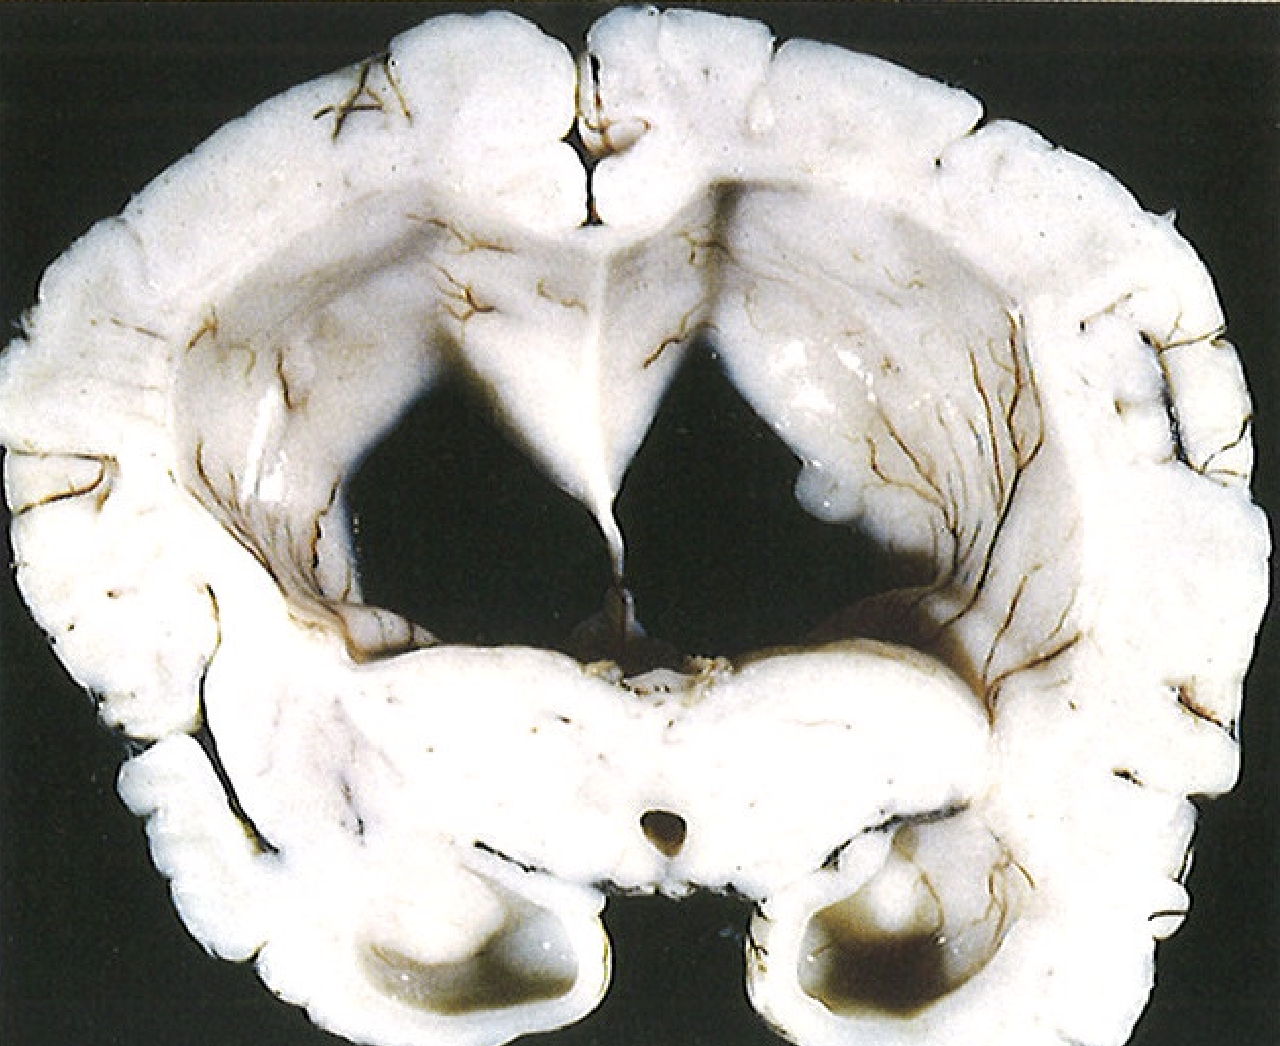

Figura 28.2 Hidrocefalia. Ventrículos laterales dilatados observados en corte frontal a través de la región centraI del tálamo.

Si la hidrocefalia se produce en un niño antes del cierre de las suturas craneales, la cabeza aumenta de tamaño. Por el contrario, después del cierre de las suturas, la hidrocefalia produce expansión de los ventrículos y aumento de la …… intracraneal, sin cambios en el perímetro cefálico

C = nucleo caudado P = Putamen S = nucleo estriado ## Footnote En la foto de abajo hay perdida del nucleo caudado. Comparar con la foto de arriba Ventriculos dilatados por perdida de masa encefalica = hidrocefalia ex vacuo